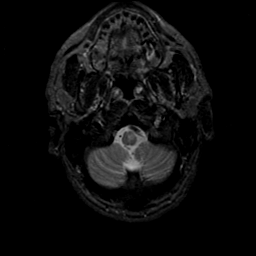

MR Study #21, November 3, 1991 -- Slice #4

[Home][Help][Clinical][Tour 1][Tour 2] Slice 4